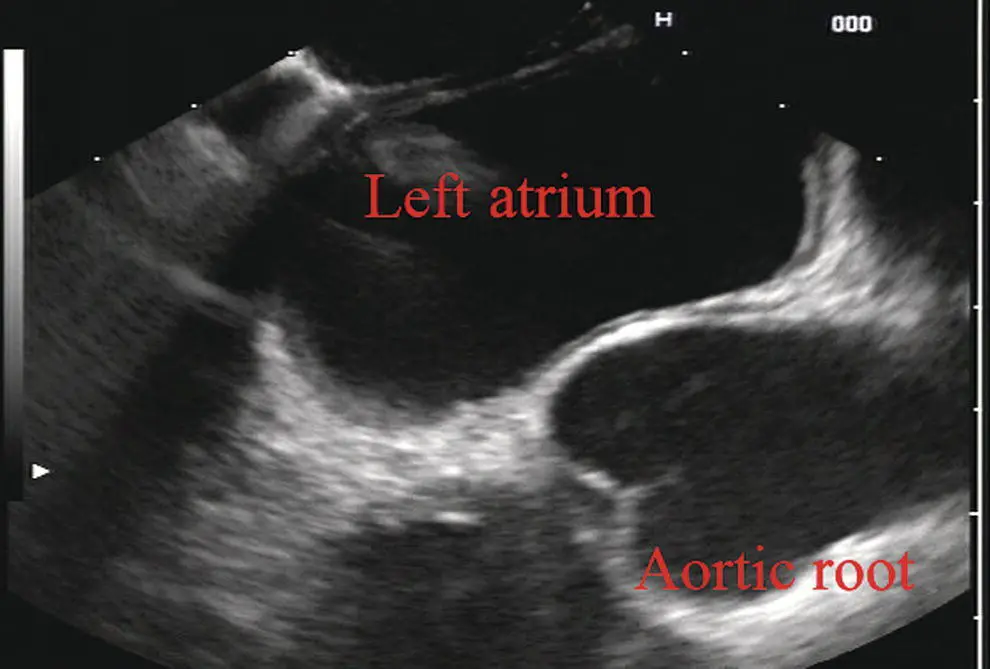

As the scope is withdrawn 3–5 cm back from the GE junction, the scope will need to be rotated 180 degrees off the aorta to see the left atrium and cardiac structures. The cardiac structure can be discerned quite readily using the linear scope. The mitral valve is just adjacent to the aortic root, which is just at clockwise rotation from the mitral valve. The aortic valve can be visualized at various angles with appropriate endoscopic manipulation given its position relative to the esophagus ( Figure 2.12).

Figure 2.12 Linear array image at the aortic root.